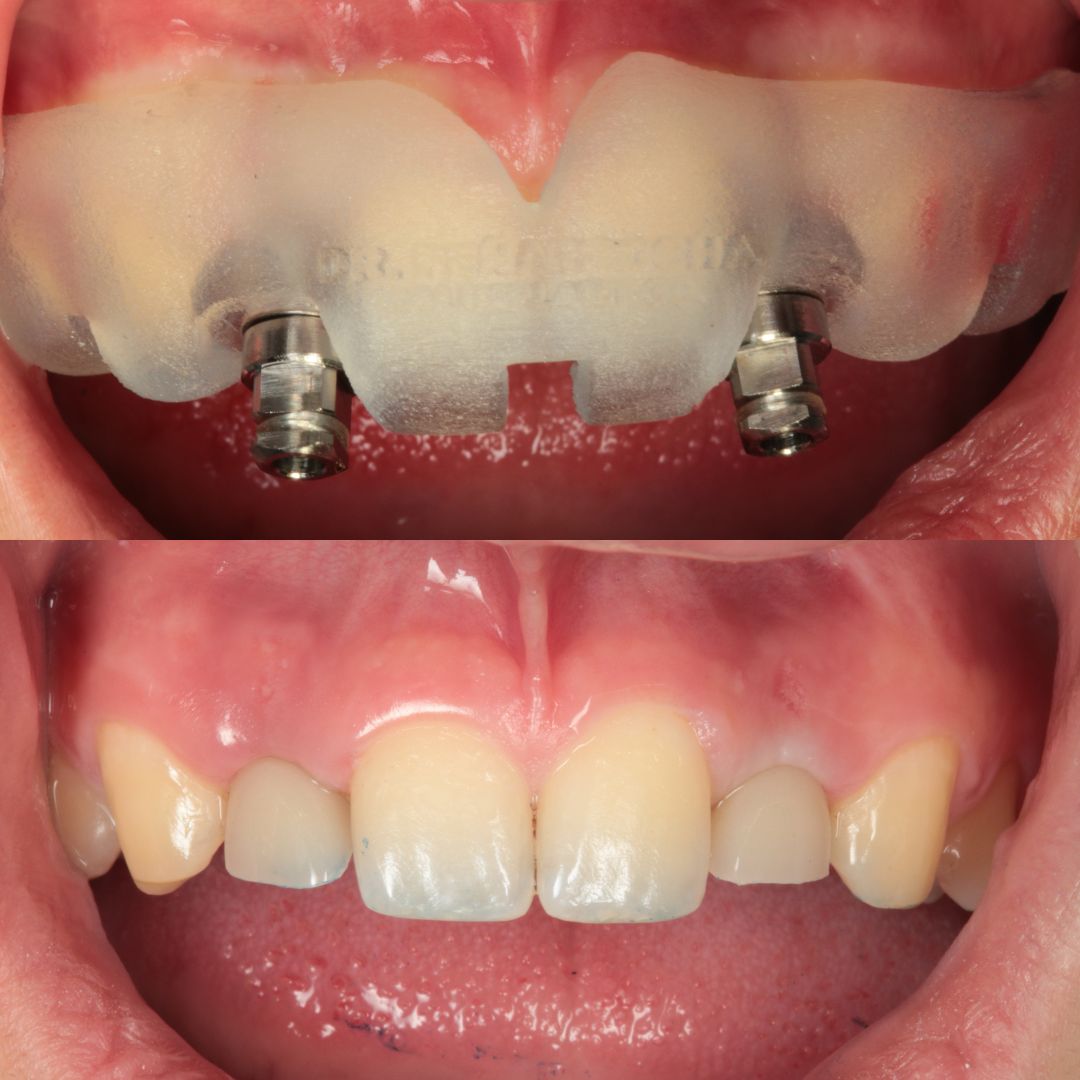

Casos de antes y después de los implantes dentales

Descubra los testimonios de nuestros pacientes tras realizarse su tratamiento de implantes dentales